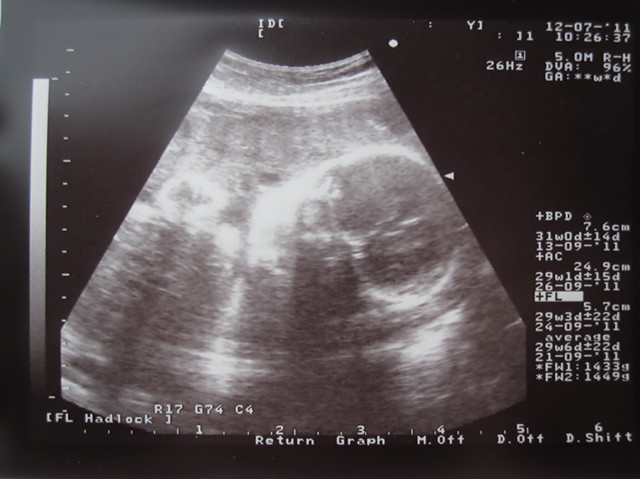

7.12 第7次B超

31周 屏幕里只能看到头了

我一直不明白那些B超的数据是什么意思

每次也就只能问BB健康吗 健康啊 OK 就走了

B超有量宝宝头直径,鼻梁长度什么的,那时医生有跟我们说的。有些记不太清楚了。